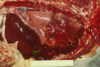

Q

This is a liver. What lesion is shown here?

A

multifocal hepatic abscesses